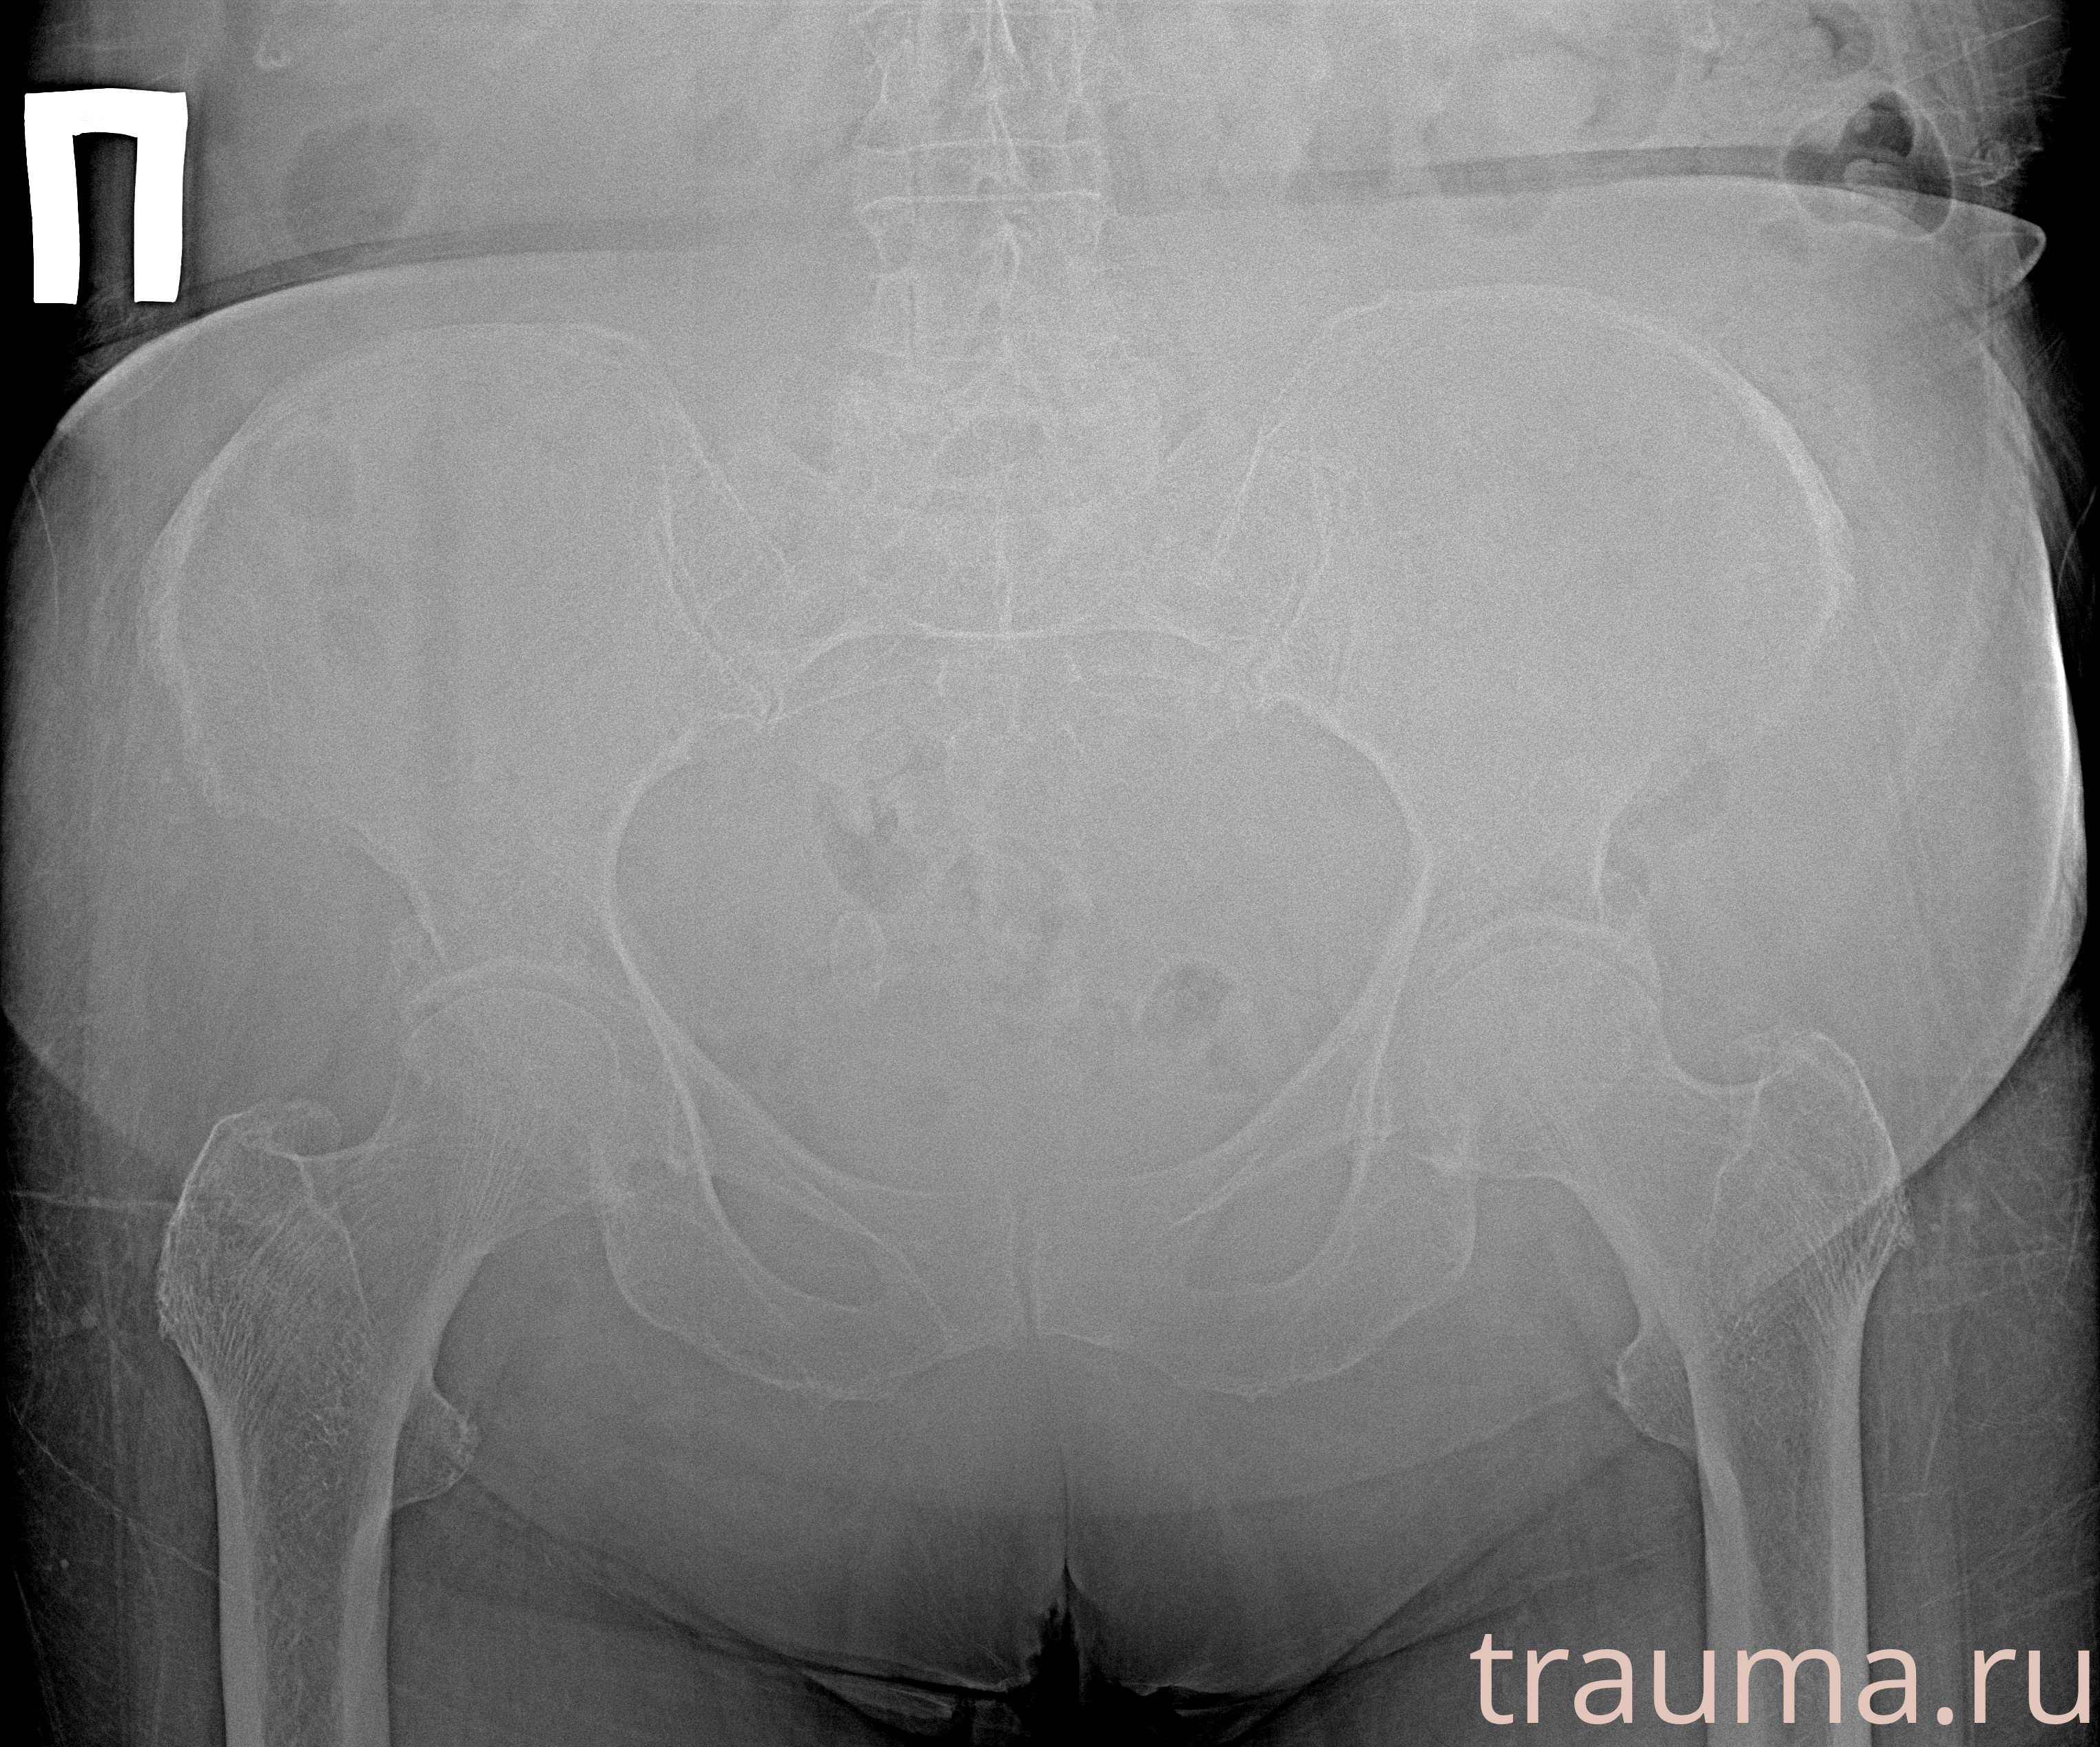

Рентгенограммы

Рентген на дому: по вашему адресу приезжает врач-рентгенолог, травматолог-ортопед с мобильным рентгеновским аппаратом, проводит диагностику травмы или заболевания, делает необходимые рентгенограммы, дает рекомендации по дальнейшему лечению. Получить качественные снимки в домашних условиях возможно благодаря уникальной методике, разработанной МосРентген Центром для института  Склифосовского